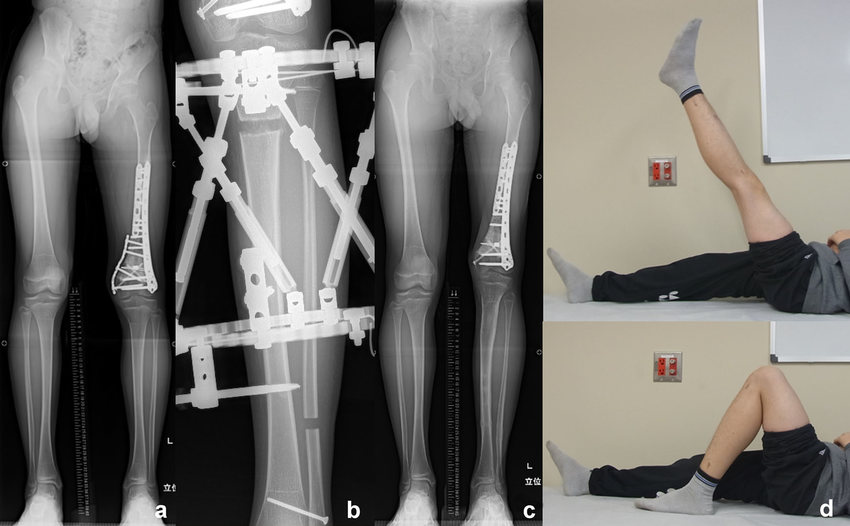

Treatment options for LLD depend on the severity of the discrepancy, the child's age, and the underlying cause. They include: